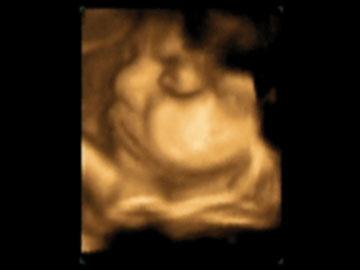

Fotografías de ecografías 4D HD/5D

Haga click sobre las imágenes para ampliar